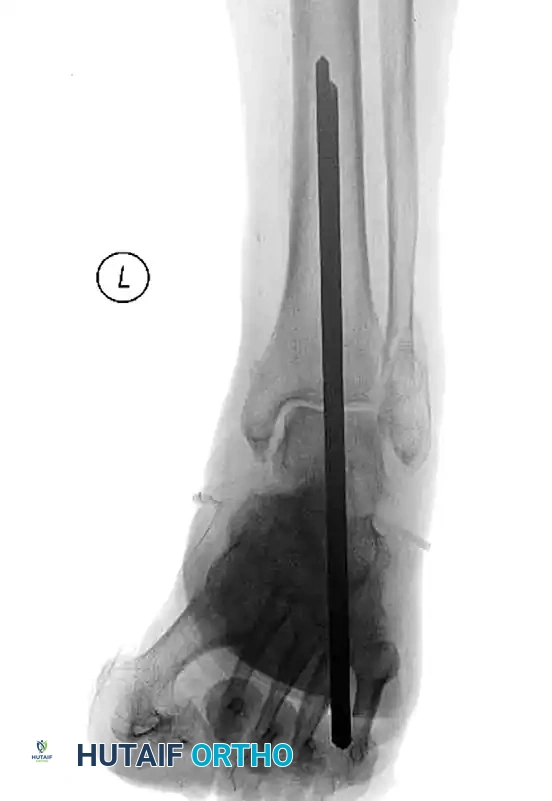

Tibiotalocalcaneal (TTC) Arthrodesis

When the ankle joint is unsalvageable due to severe Charcot destruction, realignment and extended fusion are required. A TTC arthrodesis utilizing a retrograde intramedullary nail provides a load-sharing construct that is biomechanically superior in the neuropathic patient.

Surgical Steps for TTC Nailing:

1. Preparation: The articular cartilage of the tibiotalar and subtalar joints is aggressively debrided down to bleeding subchondral bone.

2. Alignment: The foot is positioned in neutral dorsiflexion, 5 degrees of valgus, and 10 degrees of external rotation.

3. Implantation: A rigid retrograde intramedullary nail is introduced through the plantar aspect of the calcaneus, traversing the talus and into the tibial canal. Multiple locking screws are placed to secure the construct.

FIGURE 85-20 C and D: Postoperative radiographs following successful tibiotalocalcaneal (TTC) arthrodesis with a rigid retrograde intramedullary nail, restoring a plantigrade alignment.